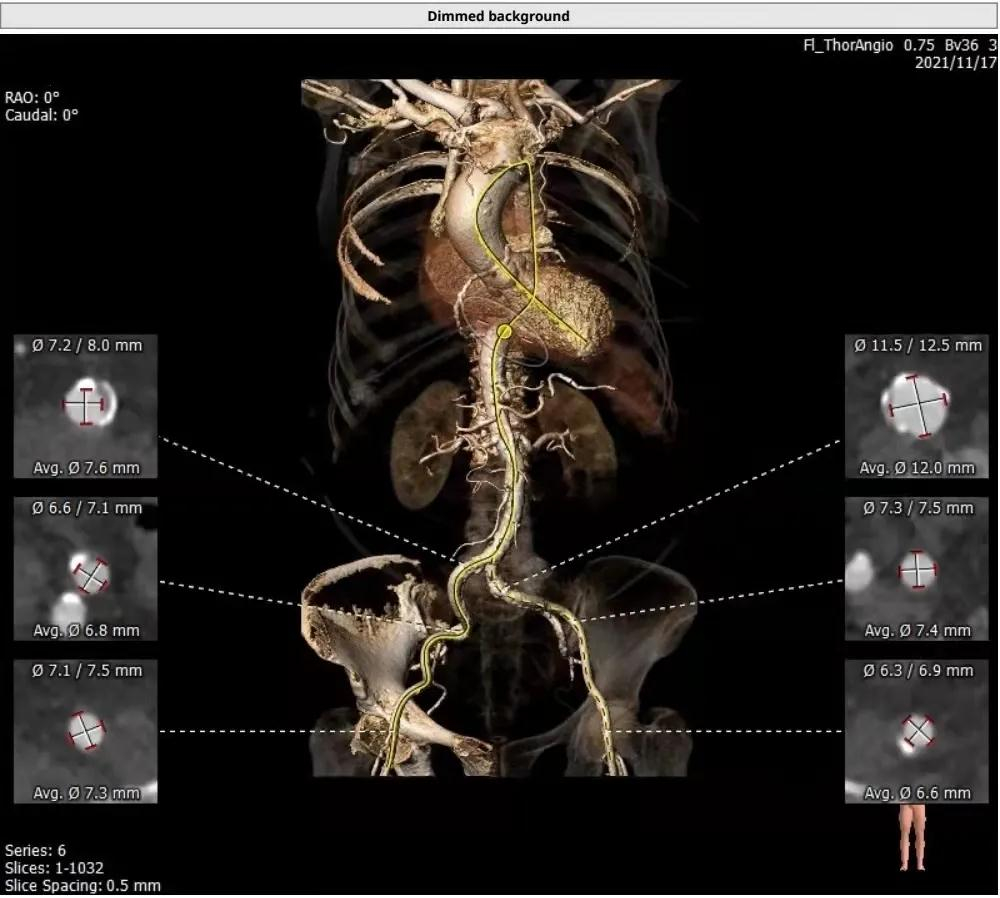

血管入路评估: